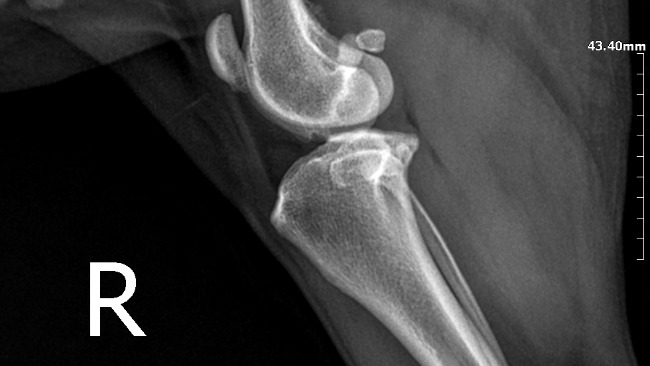

Kochani moje potrzeby schodzą na drugi plan. Moja sunia potrzebuje waszej pomocy. Eti musi przejsc operacje oraz leczenie, na które mnie niestety mnie niestac. Mogę jeździć na starym wózku, ale moi członkowie rodziny są dla mnie najważniejsi. Jestem gotowa zrezygnowac ze wszystkiego by jej pomóc.